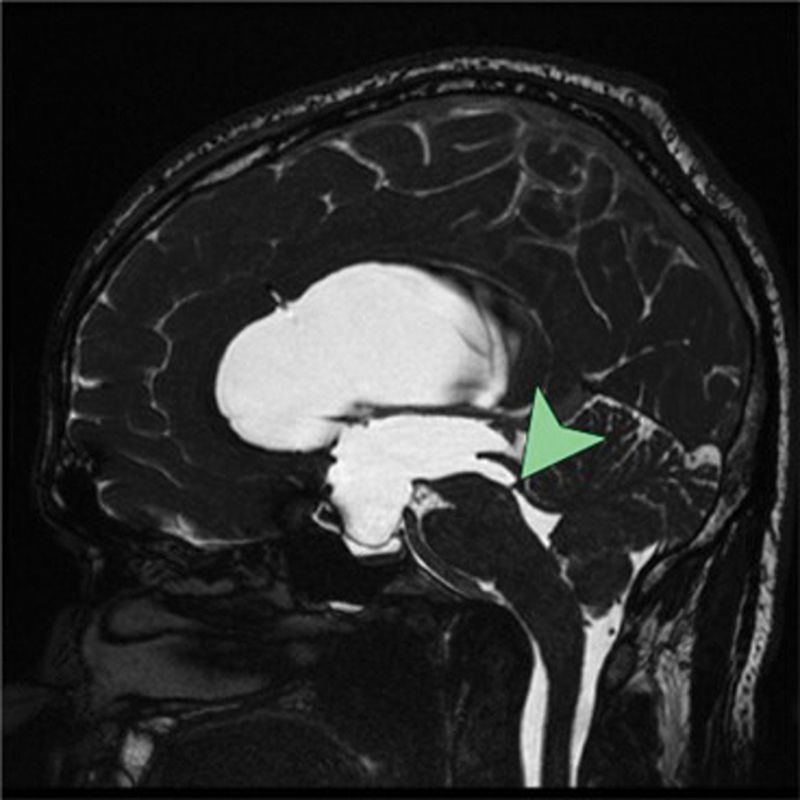

背景先天性输水管狭窄(CAS)是一种罕见的变异,被称为成人发病的CAS,其特征是在成年期出现症状。病例描述一名35岁男性主诉急性头痛和呕吐。脑磁共振成像显示急性脑积水由于输水管网。病人接受脑室腹腔分流术治疗,情况良好。他的病情因过度分流而并发硬膜下血肿,通过额顶骨开颅治疗,最终他接受了可编程瓣膜翻修。结论成人导水管狭窄的假说有待进一步研究。这将有助于阐明无症状儿童期,并通过早期识别晚期CAS,潜在地减少并发症。

Background  A rare variant of congenital aqueductal stenosis (CAS) is known as adult-onset CAS, characterized by the emergence of symptoms during adulthood. Case Description  A 35-year-old man presented complaining of acute-onset headache and vomiting. Magnetic resonance imaging of the brain revealed an acute hydrocephalus due to an aqueductal web. The patient was treated with a ventriculoperitoneal shunt and doing well. His condition was complicated by subdural hematoma as a result of overshunting, which was treated by frontoparietal craniotomy and eventually, he underwent valve revision to a programmable valve. Conclusion  Additional research is needed to gain a deeper understanding of the hypothesis related to adult aqueductal stenosis. This will help shed light on the asymptomatic childhood phase and potentially reduce complications by identifying late CAS early.